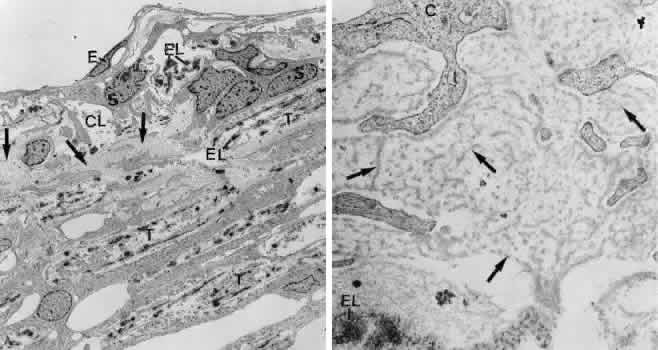

There are three different types of tendons by which the anterior ciliary muscle tips are connected with the TM or the corneosclera. Type I tendons derive from the outermost longitudinal muscle bundles and enter the sclera or the scleral spur to fix the muscle to the external tunica of the eyeball (Fig. 18). Type II tendons pass the scleral spur to anchor within the TM. They consist of elastic-like fibers that bend into the outer part of the TM and finally join the subendothelial network of elastic-like fibers described earlier. Type III tendons are of collagenous nature. They represent broad, elongated bands that penetrate the TM and insert within the corneal stroma.21,42 The tendons represent the main fixation of the entire ciliary muscle system to the external tunica of the eyeball and therefore seem to be important in the accommodation mechanism. The tendons may also help to expand the system of trabecular lamellae, so that the intertrabecular spaces remain open or enlarge if the ciliary muscle moves forward and inward. Regarding the outflow resistance, this would have little effect in normal eyes.

Fig. 18. Connections of the ciliary muscle (CM) with the trabecular meshwork (TR). Note the different types of muscle tendons (T) connected with the cornea or the elastic-like fiber network of the cribriform layer (EL), which on the other hand is connected with the inner wall endothelium (E) of Schlemm's canal (Sc) by connecting fibrils (CF). SP, scleral spur.